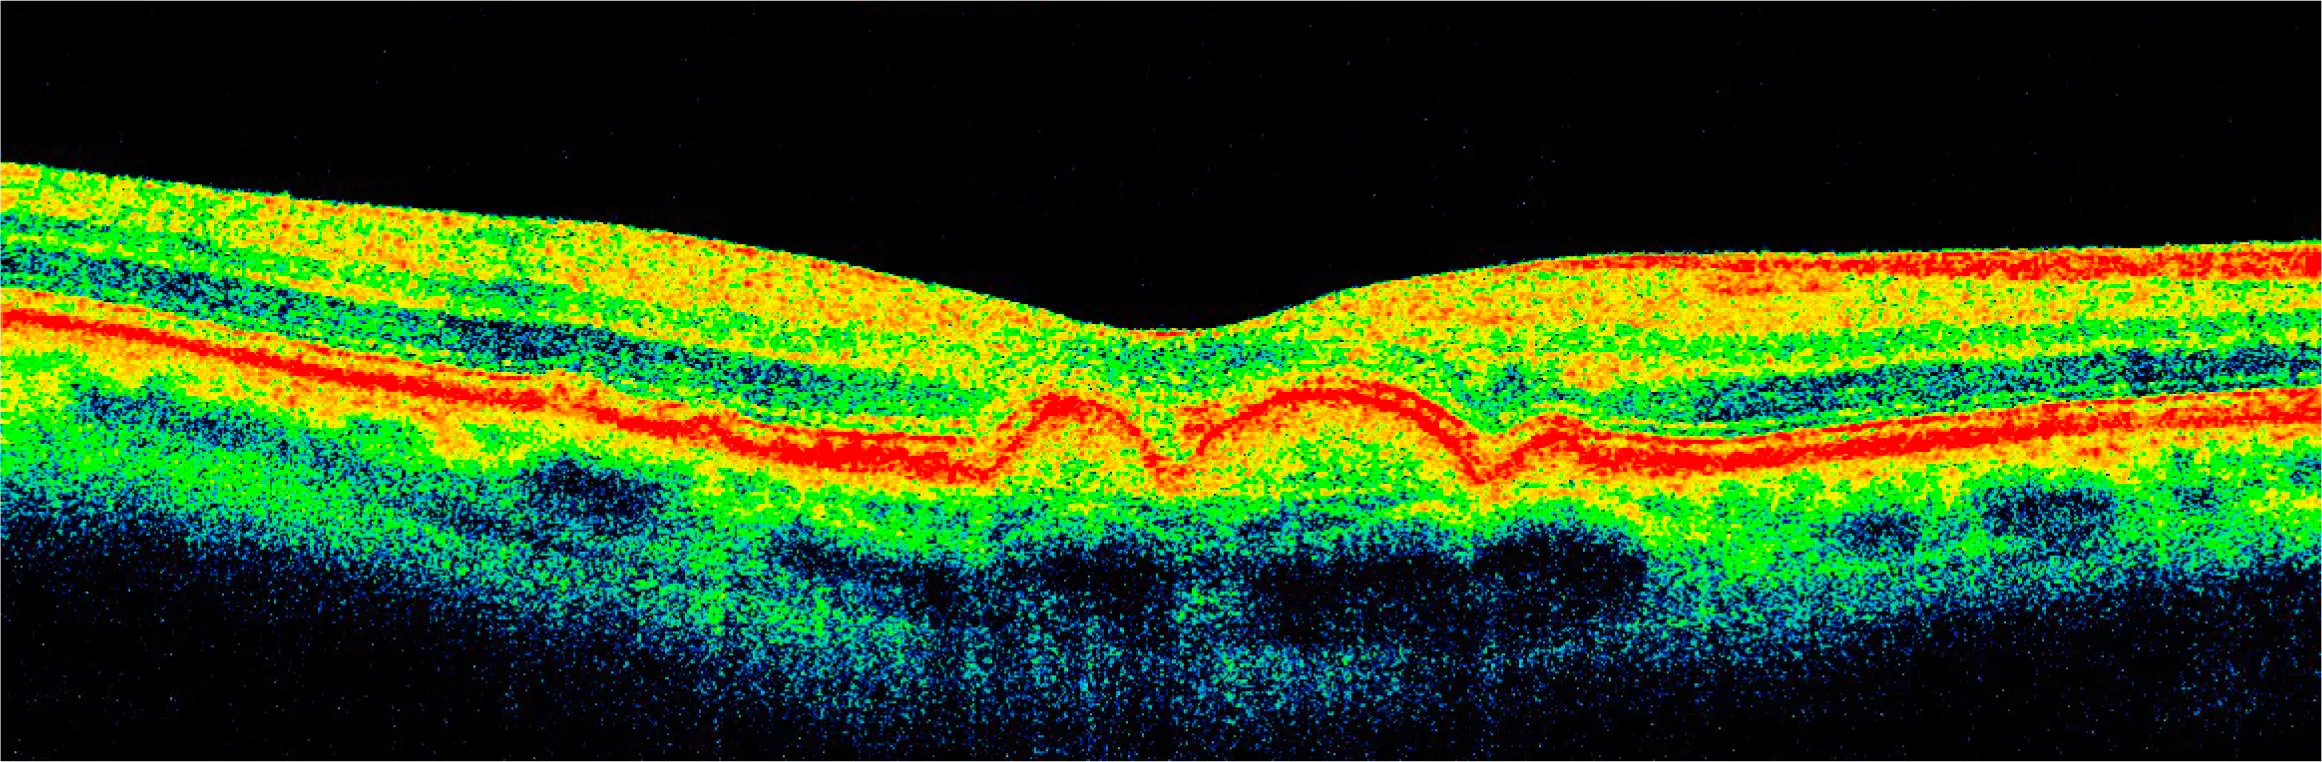

At her 6-month follow-up, her drusen were decreased by about 70%.

It inspired me to use AI to turn the OCT scans into a video to help visualize the healing process...

After years of deterioration on AREDS2 and other more conventional nutritional supplements, drusen largely resorbed in 15 months on a higher priced broad spectrum botanical/nutritional regimen, restoring 20/20 visual acuity in each eye as well as distortion-free Amsler Grids.